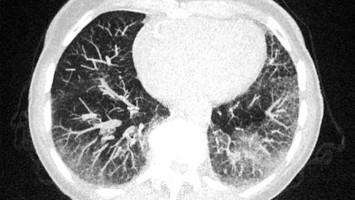

e.Med Interdisziplinär Icon, Search Icon, Digitales Blutdruckmessgerät/© Kotchakorn / Stock.adobe.com (Symbolbild mit Fotomodell), Subunguale Exostose/© T. Jansen, Junger Mann trinkt Wasser/© Syda Productions / stock.adobe.com (Symbolbild mit Fotomodell), Untersuchung des Beins eines Patienten/© Visionär / Fotolia, Illustration zur künstlichen Intelligenz/© Toowongsa / Stock.adobe.com (Symbolbild mit Fotomodell), EKG bei RIVA-Stenose/© S. Grautoff, Tee aus Linghzi-Pilzen/© krungchingpixs / Getty Images / iStock, Schmerzhafte Schwellung des linken Ellenbogens/© C. Raschka, Person hält sich den Bauch/© anut21ng Stock / stock.adobe.com (Symbolbild mit Fotomodell), Acne inversa bei einem Patienten/© I. Güler, Frau sitzt besorgt beim Arzt und hält sich den Kopf/© M+Isolation+Photo / Stock.adobe.com (Symbolbild mit Fotomodell), Tinospora cordifolia/© SUBASCHANDRA / Stock.adobe.com, CT einer Lunge mit Milchglastrübungen/© Kremer P et al. / all rights reserved Springer Medizin Verlag GmbH